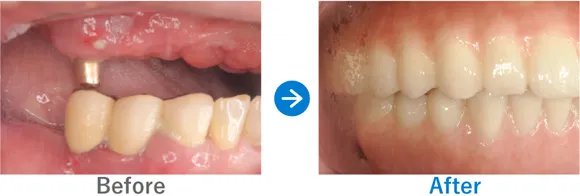

残存歯の動揺、義歯の不適合、重度の歯周病

上顎 オールオン4、下顎 オールオン4

残っている歯がぐらぐらする感覚があり、使用中の義歯が合わなくなってきているため、インプラントを検討し来院されました。

治療結果

もともと重度の歯周病があり、残っている歯が動いてしまい歯が前に出ているような並びになっていました。そのため、正常な位置で嚙み合わせるように設計し、オールオン4治療を行いました。歯周病に加え喫煙も続けているため、インプラント周囲炎にはとくに注意が必要です。